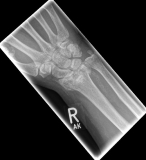

Often the inspection of the wrist already shows a suspected diagnosis. The accident mechanism must be clarified and after the physical examination, X-ray images of the wrist must be made in 2 levels.